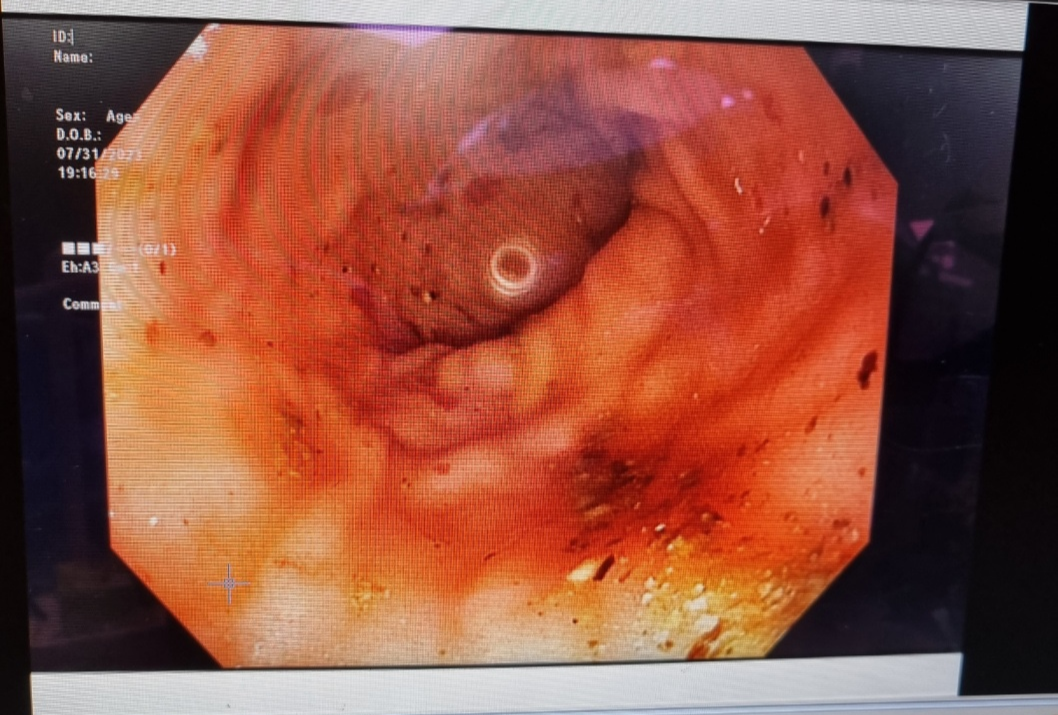

이렇게 병원을 바꿔가면서 6개월정도를 고생하다가 결국 2차 병원에서 CT와 대장내시경을 했습니다.

2차 병원은 분당리더스병원을 갔습니다. 일반적인 검사들 (피검사, x-ray, 초음파 등) 모두 정상으로 나왔습니다. 여기서도 출혈성 장염을 의심하고 새로운 약을 써본다고 하셨음. 하지만 약이 듣는가 싶더니 또 피똥을 심하게 싸기 시작. 이제는 거의 한 달째 다니고 있는데 마지막이라고 생각하고 CT와 대장내시경을 해보기로 했습니다.

이 두 검사를 하기위해서는 마취를 해야하는데 소형견이거나 나이가 많은 경우 마취 후 깨어나지 않을 수 있는 위험성이 어쩔수없이 있다고 해요. 아무튼 그렇게 동의서 작성후 검사가 들어갔고, 결과는 정말... 다행이면 다행이지만 아무 이상이 없었습니다.

위, 대장 전부 깔끔했지만 위벽과 대장벽이 굉장히 얇아져있어서 출혈이 있는 것 같다고 합니다. 위벽, 대장벽이 얇아지는 건 강아지의 나이 때문에 그런 경우가 많다고 해요. 위장보호하는 약과 위, 대장에 무리를 주지 않는 음식으로 바꿔 먹이면서 관리하고 있습니다.

위와 대장에 종양이나 다른 이상은 없었지만 위벽과 대장내벽이 얇아져 음식물이 지나가면서 위와 장에 출혈이 생겨서 변에 피가 묻어 나오는 거였다. 의사 선생님 말로는 나이가 들면서 위와 대장이 약해졌고 더 이상 약물치료나 다른 치료를 통해 할 수 있는 게 없다고 하셨다. (그전에 약물치료를 2주간 했었음)